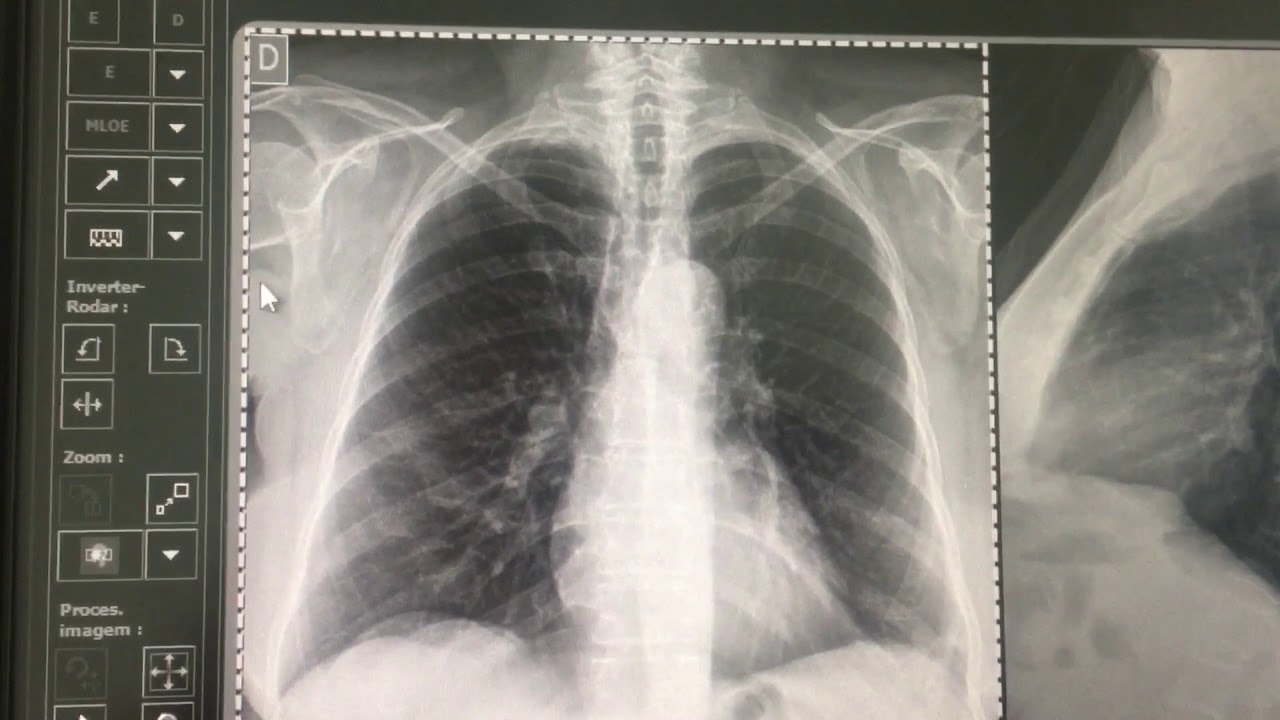

necessidade do equipamento de muita potência para ser utilizado numa placa dr quando a gente utiliza o cr quando for de qualidade da imagem principalmente alguns artefatos formados por baixa técnica falando grosseiramente assim a grosso modo a gente fala que houve baixa técnicas e artefatos formado por baixa técnica como eu percebo isso na imagem a imagem produzida vamos a um exemplo por um cr num paciente grande quanto maior for esse paciente maior a técnica que eu preciso utilizar mais radiação mais potência mais penetração né se eu for utilizar só fazer uma radiografia de um paciente grande

utilizando um sistema de baixa potência numa forma de captação pouco sensível eu tenho talvez um artefato que a gente chamava de granulação essa imagem ela fica granulado ela perde nitidez ela perde qualidade isso vai comprometer também o resultado final no tratamento e no prognóstico na conduta do caso deste paciente se você gostou desse vídeo dá o seu like assim nosso canal fique atento às novidades [Música]